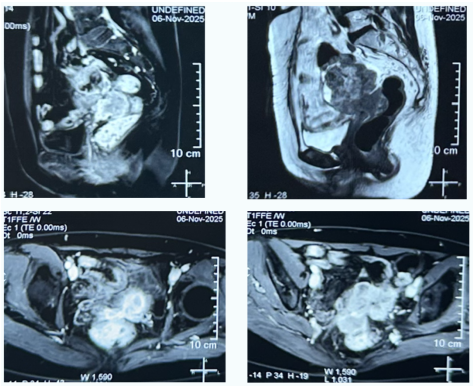

62岁的李女士(化名),既往有宫颈癌、乙状结肠癌手术史,最近出现了血尿的症状,在家人的陪同下来到哈医大一院群力院区就诊。经进一步检查发现,李女士盆腔内存在一约8.1×6.6cm的囊实性占位,肿瘤侵犯膀胱后壁、直肠、部分回肠、乙状结肠、左侧输尿管及阴道断端,并伴有左侧输尿管扩张及盆腔淋巴结肿大,病情极为复杂。